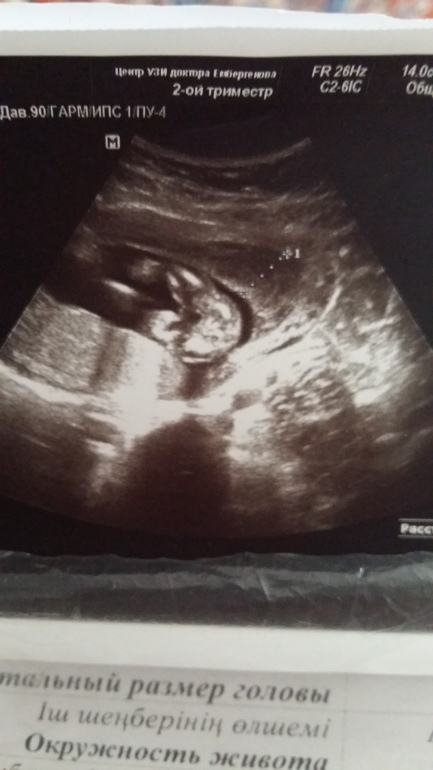

и вот распечатали пирожок))))